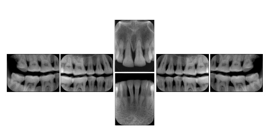

3. A dental provider wishes to capture a series of DICOM IO images for the patient’s dentition. The tooth morphology, teeth are divided into molars, premolars, canines and incisors, and a number of images for each jaw. The anatomic information was captured utilizing the triplet of schema. This standard code sequence is based on ISO 3950-2010, Dentistry - Designation system for teeth and areas of the oral cavity.

Every IO image should have anatomic information either through the primary or modifier sequence.

In most standard cases, images are oriented in structured layouts. These structured displays are useful to be shared between providers for reference purposes.

Table OO.1.1-1 shows structured display standard templates, where Viewset ID is based on the Japanese Society for Oral and Maxillofacial Radiology (JSOMR) classification provided by JIRA (Japan Medical Imaging and Radiological Systems Industries Association, www.jira-net.or.jp). Expected or typical teeth to be imaged location, region and designation codes are based on ISO 3950-2010, Dentistry - Designation system for teeth and areas of the oral cavity. For all the hanging protocols listed in OO.1.1-1, the value to use for Hanging Protocol Creator (0072,0008) is "JSOMR" and the value to use for Hanging Protocol Name (0072,0002) does not include "JSOMR" (e.g., "DL-S001A", not "JSOMR DL-S001A").